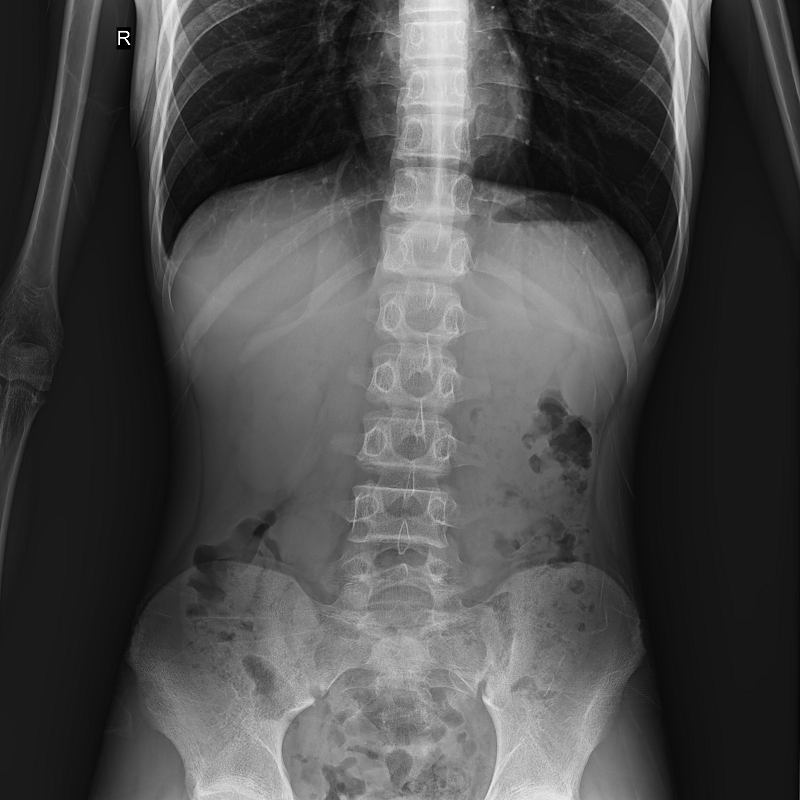

集靜態(tài)DR攝影與動(dòng)態(tài)的透視、造影功能于一身,可進(jìn)行頭部、胸部、腹部和四肢等部位的DR靜態(tài)攝影、各種動(dòng)態(tài)及造影檢查,還能在可視的情況下完成高清DR點(diǎn)片,有效避免傳統(tǒng)靜態(tài)DR盲拍造成的漏診和誤診,滿足多種臨床診斷需求。

搭載17x17英寸動(dòng)態(tài)平板探測(cè)器,動(dòng)態(tài)幀率高達(dá)30幀/秒,突破傳統(tǒng)盲拍局限,通過動(dòng)態(tài)實(shí)時(shí)連續(xù)成像,對(duì)于重疊部位、易被遮擋的病灶進(jìn)行多角度動(dòng)態(tài)觀察,瞬時(shí)實(shí)現(xiàn)高清點(diǎn)片,提升篩查診斷的精準(zhǔn)性。

● 圖像拼接

系統(tǒng)可以識(shí)別曝光圖像,無需設(shè)置識(shí)別點(diǎn)即完成精準(zhǔn)拼接,呈現(xiàn)大范圍完整影像。